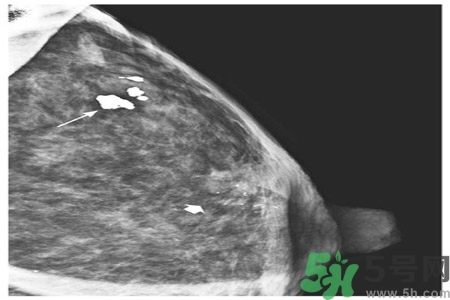

乳腺鈣化部位

了解鈣化部位應(yīng)強(qiáng)調(diào)多方位、多角度觀察。良性鈣化灶,多發(fā)生在纖維組織、脂肪、血管、大汗腺、皮膚等乳腺間質(zhì)內(nèi),乳腺實質(zhì)內(nèi)少見。惡性鈣化則多發(fā)生于乳腺實質(zhì)內(nèi),泥沙樣鈣化多發(fā)生在乳腺小葉腺泡內(nèi),小桿狀鈣化多發(fā)生在導(dǎo)管內(nèi),小叉狀鈣化則多位于末支小導(dǎo)管內(nèi)。

乳腺鈣化與腫塊的關(guān)系

鈣化可與腫塊并存,也可獨(dú)立存在;既可發(fā)生在病變內(nèi),也可獨(dú)立于腫塊之外。90%的導(dǎo)管原位癌是通過X線鉬靶照片發(fā)現(xiàn)的,且僅以乳腺內(nèi)鈣化作為惟一的表現(xiàn)形式。這是由于原位癌中央發(fā)生不規(guī)則壞死引起的鈣鹽在導(dǎo)管內(nèi)沉積或腫瘤細(xì)胞分泌而呈形態(tài)各異的的表現(xiàn)。